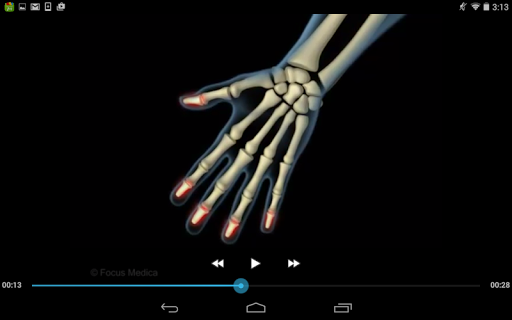

The FOCUS Animated Pocket Dictionary of RHEUMATOLOGY is the first ever animated dictionary in the subject. A valuable reference for physicians and students alike, it covers 100 rheumatology related terms and definitions. All the definitions have been graphically described with the help of 3D animations and are accompanied by text definitions.

The Focus Animated Pocket Dictionaries are the world’s first ever animated dictionaries that provide definitions of medical terms with the aid of realistic and narrated 3D animations, complimented with text definitions. Terms arranged alphabetically making definitions easy to search. These unique visual dictionaries are excellent reference sources for health professionals, students and health consumers. The videos play independent of the internet once downloaded.